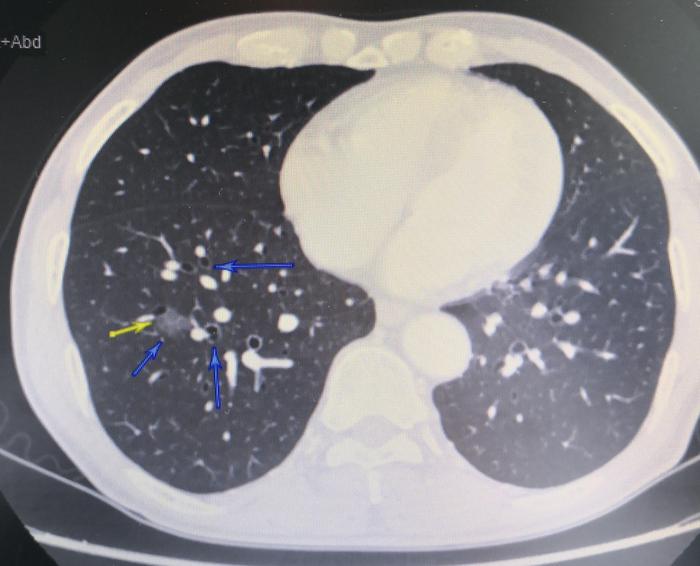

上图(图4),黄色箭头和左边蓝色箭头指示的是右下肺基底段磨玻璃结节,磨玻璃结节内部图案出现乌龟壳上的花纹样改变。上边蓝色箭头指示的是右下肺前基底段支气管。右下方蓝色箭头指示的是右下肺外基底段支气管。这张CT说明这个磨玻璃结节位于右下肺的前基底段支气管和右下肺外基底段支气管之间,也就是说,位于右下肺的前基底段和外基底段中间。

上图(图5),是图4的放大图。黄色箭头和左边蓝色箭头指示的是右下肺基底段磨玻璃结节,磨玻璃结节内部图案出现乌龟壳上的花纹样改变。上边蓝色箭头指示的是右下肺前基底段支气管。右下方蓝色箭头指示的是右下肺外基底段支气管。